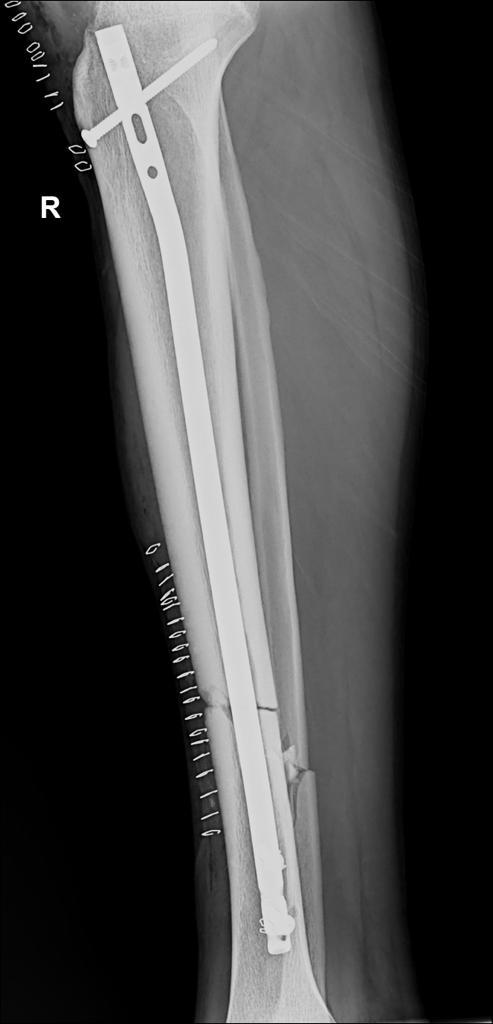

Nyuma y’umunsi umwe umunyezamu Kimenyi Yves wa AS Kigali agize imvune ikomeye cyane amagufwa y’agatsitsino agatandukana, ubu yamaze kubagwa.

Amakuru meza ahari ni uko Kimenyi Yves yabazwe neza n’umuganga kabuhariwe mu kunga amagufa ukorera mu bitaro by’inkuru nziza biri Gikondo.

Nk’uko byatangajwe na AS Kigali, mu mafoto bashyize hanze, ubu igufwa ryatandukanye uyu muganga yamaze gushyiramo insimburangingo izatuma igufwa ryongera guhura neza.